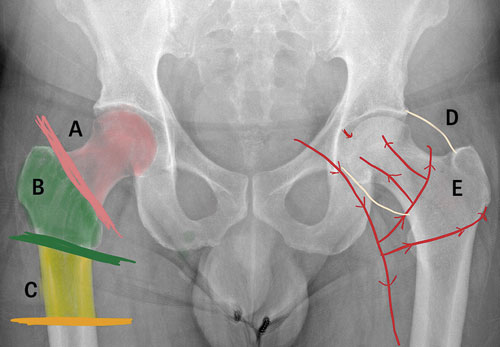

Anatomi. Höftfrakturer delas in i tre kategorier: cervikala höftfrakturer (lårbenshalsfrakturer), pertrokantära och subtrokantära frakturer. Cervikala höftfrakturer är vanligast och utgör cirka hälften av alla höftfrakturer. Av dessa är majoriteten dislokerade (felställda).

Subtrokantära frakturer är mer ovanliga och utgör knappt 10 procent [1].

Kärlförsörjning och frakturindelning efter anatomi. Höger höft: A) cervikala frakturer, B) pertrokantära frakturer, C) subtrokantära frakturer. Vänster höft: D) schematisk bild över kapselns utbredning samt E) blodförsörjning till caput och collum femoris.